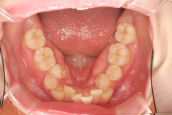

初診時です

大学病院では顎を切る手術の矯正になると言われ、同時に小さな奥歯を4本抜歯する必要があると言われたそうです。なぜ このような乱ぐい歯になったのでしょう?その考察がなく、見た目の乱ぐいだけを考えたのでは、本当の意味での治療にはならないと思います。なぜ このような成長方向になったのでしょうか。

それには奥歯の高さの成長の不足があります。そこをコントロールして原因を取り除くことによって、成人になってからも本来の正しい方向に進みます。